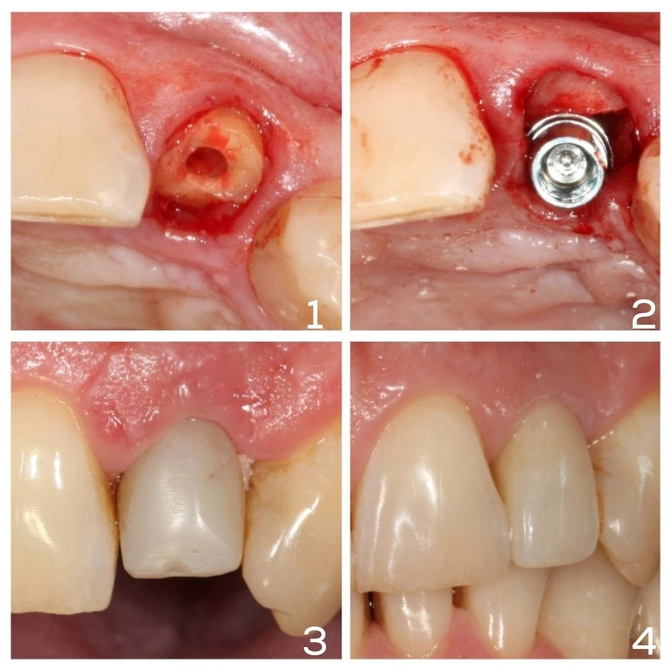

Имплантация и протезирование центрального зуба

Имплант+коронка в зоне улыбки.

Переходим к клиническому случаю.

У пациента перелом бокового резца — смотреть больно.

Здоровый нормальный зуб и, увы, придется заменить его имплантом.

➖Восстановить коронкой не получится, т.к. перелом глубокий, коронковая часть утрачена.

➖Подрезать десну тоже не выйдет — будет слишком большой дефект на нёбе.

➖Даже вытянуть зуб ортодонтически не получится, потому что корень короткий.

✔️Выход один — удаляем корневую часть зуба и одномоментно устанавливаем имплант.

Сверху фиксируем временную коронку, пока изготавливается красивая постоянная.

Временная коронка короче остальных зубов, чтобы не задевать ее при кусании, жевании и разговоре.

В финале лечения получаем крутой результат✔️

Керамическая коронка идеально вписывается в зону улыбки.

Эстетика не пострадала, искусственный зуб не отличить от родных.